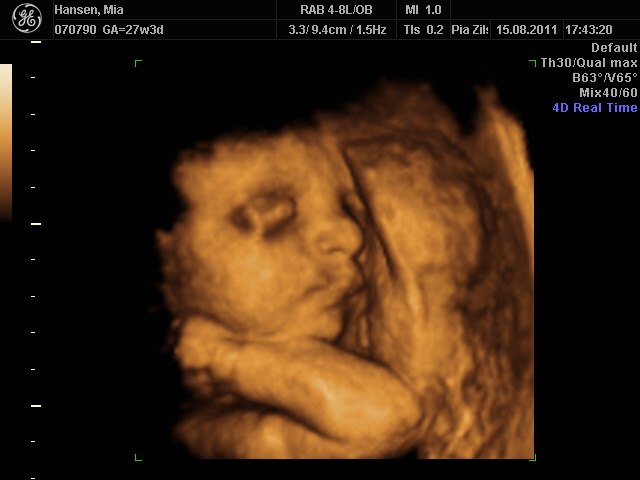

Fantastisk oplevelse. Lillepigen er bare så fin  en rigtig putte-pige

her kommer lidt billeder

Mia 27+3